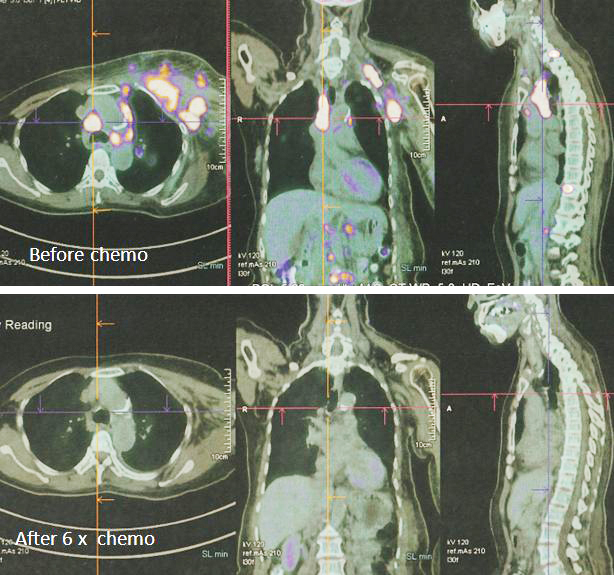

8. PET scan on 14 April 2022 showed good response indeed.

1. Amazing results of chemotherapy. Compare these three pictures –

Left: After surgery Lucy was on alternative therapy, refusing to undergo chemotherapy. The result was extensive metatastasis (middle). Right: Lucy has no choice but to go for chemotherapy. The outcome of 6 cycles of chemotherapy was just fantastic! In my 25 + years dealing with cancer patients, I have never seen such a great outcome of chemotherapy. Salute the oncologist! You rescued her!

In fact, the results were so unbelievable that one is tempted to ask if it is for real and not a fake? My answer is NO, detailed study of the PET scan results below are real! Study the images carefully – those before and after  chemotherapy.